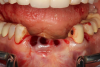

Case 3. TRAUMA: SINGLE Central INCISOR-GUIDED Smile

A 23-year-old man reported to the dental practice on January 3. Apparently, while on vacation and celebrating the New Year, the patient experienced a loss of equilibrium and found himself horizontal in the crosswalk. When surveying the damages, his friends noticed he was missing tooth No. 8. Those who were involved were not able to find the missing maxillary central incisor. The young man was eventually seen about 3 days after the trauma. A CBCT radiograph, study models, and photographs were collected, and teeth Nos. 6 through 10 were immobilized with composite and 20 x 20 orthodontic wire (Figure 14). The CBCT and photos were emailed to the dental laboratory, and the analog intraoral impression with a centric occlusion bite registration was sent via ground transportation. Due to the nature of the trauma, the laboratory and the author expeditiously converted the analog diagnostics and merged all the patient's data sets to develop the plan. Based on the 3D data sets, the laboratory and the dentist were able to accurately assess the volume of bone and soft tissue remaining after the trauma. The volume was still intact and soft tissue was plentiful (Figure 15 and Figure 16).

Fig 14. Immobilization splint placed 3 days after trauma.

Figure 14

Fig 16. Preoperative periapical radiograph on the day of surgery.

Figure 16